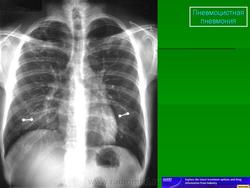

Рентгенологическая картина ПП

На рентгенограмме грудной клетки, как правило, выявляются двусторонние симметричные интерстициальные инфильтраты, однако в 20% случаев патологические изменения отсутствуют (Am J Roentgenol 1997; 169: 967). В прикорневых отделах легких определяется облаковидное понижение прозрачности, мелкоочаговые тени, располагающиеся симметрично в обоих легочных полях в виде крыльев бабочки. Такие изменения получили название облаковидных, пушистых инфильтратов, создающих вид «ватного» легкого. В ряде случаев встречаются атипичные рентгенологические признаки (инфильтраты периферической или латеральной локализации, лобарные или сегментарные, инфильтраты, располагающиеся в верхних отделах легких, как при туберкулезе, единичные в виде узлов). Довольно часто развивается пневмоторакс, который является характерным осложнением этого заболевания [1, 5-8]. На рис. 1, 2 приведены рентгенологические изменения легких у больных ПП.

Использование метода КТ позволяет обнаружить диффузные изменения в легочной ткани. Отсутствие патологических изменений на снимках, полученных методом КТ с использованием тонких срезов, не является основанием для исключения ПП [1, 5-8].